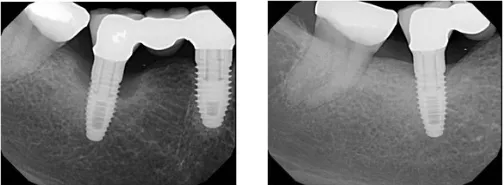

Regenerative Therapy

Before & After